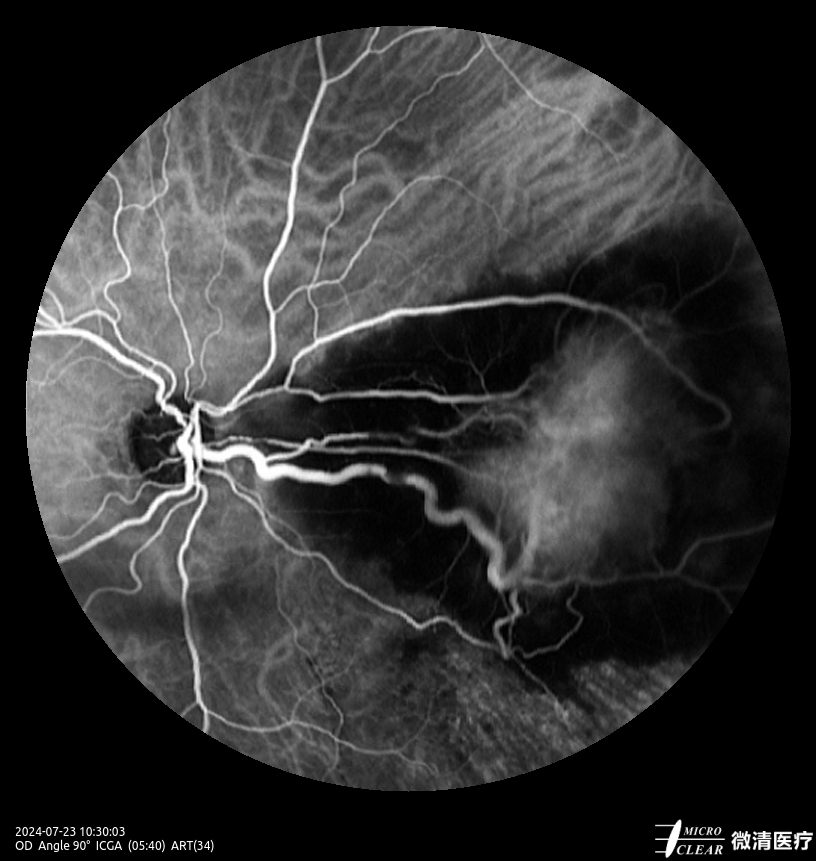

- Fundusfluoresceïne-angiografie (FFA)

- 135° WA (Groothoekangiografie) – in één opname

Confocale Scanning Laser Oftalmoscoop (CSLO)

- Combinatie van drie confocale laserbronnen voor maximaal contrast en getrouwheid.

- Verbeterd confocaal ontwerp zorgt voor een betere scheiding van de netvlieslagen en verbeterde penetratie door cataract en oculaire troebelingen.